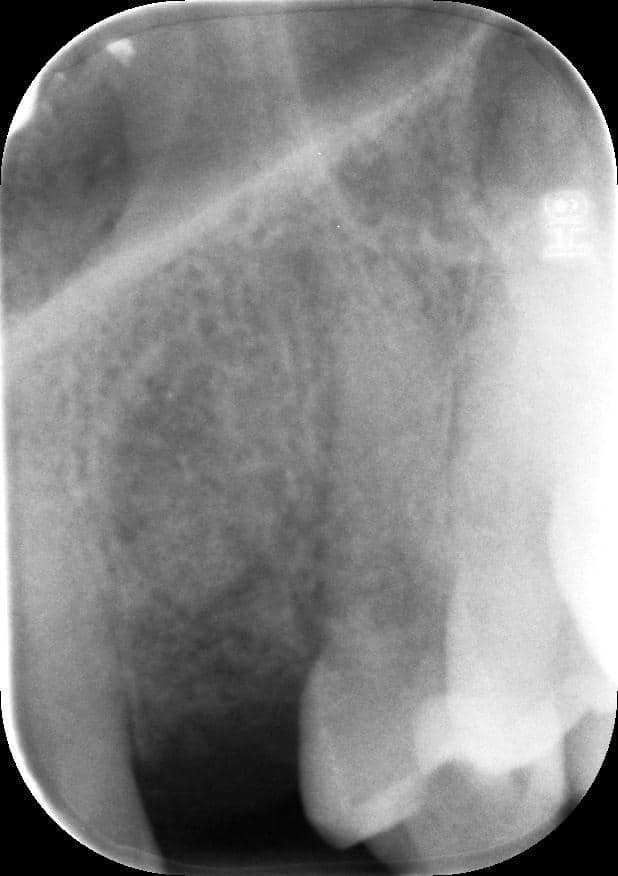

rx follow up 18 month post loading